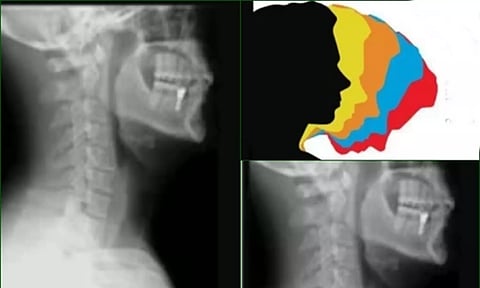

The syndrome can be defined as where the neck muscles become strained and stiff, causing long-term spinal complexities, the experts said.

"Poor posture has become the most common cause of back and neck pain among our OPD patients. Remarkably, nearly 70 per cent of our OPD patients fall into this category. Poor screen etiquette is also a leading contributor to such pain. People often use their gadgets with their neck bent for prolonged periods, leading to a condition called "text-neck syndrome. Individuals between the ages of 25 and 45 are the most commonly affected by postural back pain," said Dr Tarun Suri, Head of Spine Surgery at Amrita Hospital Faridabad.

Studies show that poor posture is the primary cause of neck and back pain in young and mid-age individuals, leading to work loss, hospital visits, and treatment expenses. Over time, it damages spinal discs, causes muscle spasms, and may lead to chronic pain, disc degeneration, and even surgery in severe cases.

The leading factors behind bad posture are poor workplace ergonomics, which entail long hours of sitting without proper chair and desk height, putting significant stress on the lower back and neck. Chronic stress can be extremely detrimental to one's spinal health. Neck, upper back, and shoulder muscles tend to tighten due to stress, which can lead to misalignment and poor posture, the doctor said.